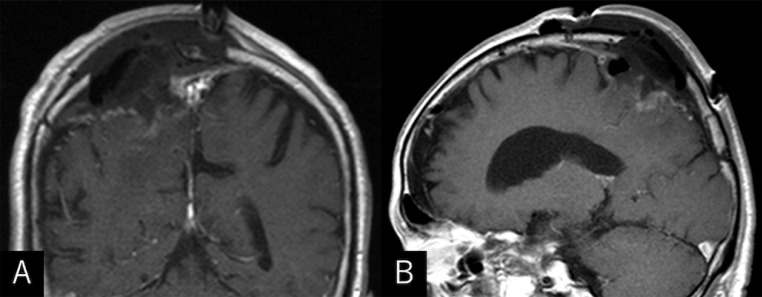

Fig. 2.

Axial T1- (A), T2-weighted (B), and postcontrast coronal (C) and sagittal (D) MRIs showing an intensely enhancing extra-axial mass. It appears isointense on T1- and hyperintense on T2-weighted sequences, respectively, broad-based on the convexity dura mater, and measuring 52 × 46 × 48 mm in maximal dimensions, with a portion upwardly protruding into the eroded skull.

Postcontrast coronal (A) and sagittal (B) MRIs showing a total resection of the tumor.